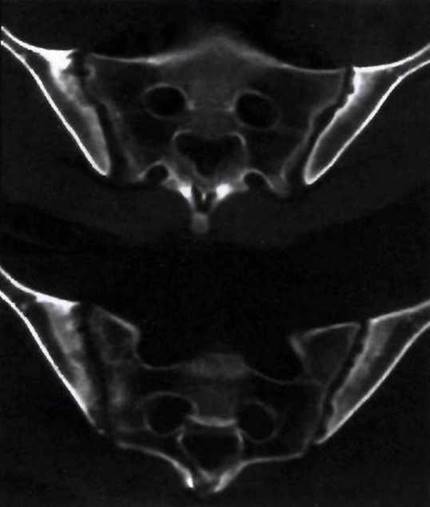

Рис. 21-5. Компьютерная томография тазобедренных суставов.

Рис. 21-7. Компьютерная томография коленных суставов.

Рис. 23-22. Двусторонний сакроилеит у больного ЮАС: эрозии, расширение щелей крестцово- подвздошных сочленений, субхондральный склероз. Патологические изменения определяются в обеих сочленяющихся костях, но более выражены в подвздошных костях.